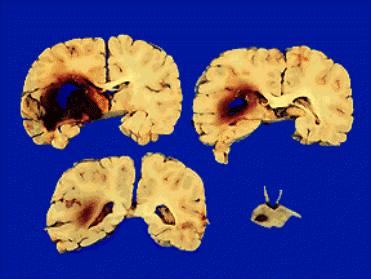

Рис.4. Внутримозговые кровоизлияния